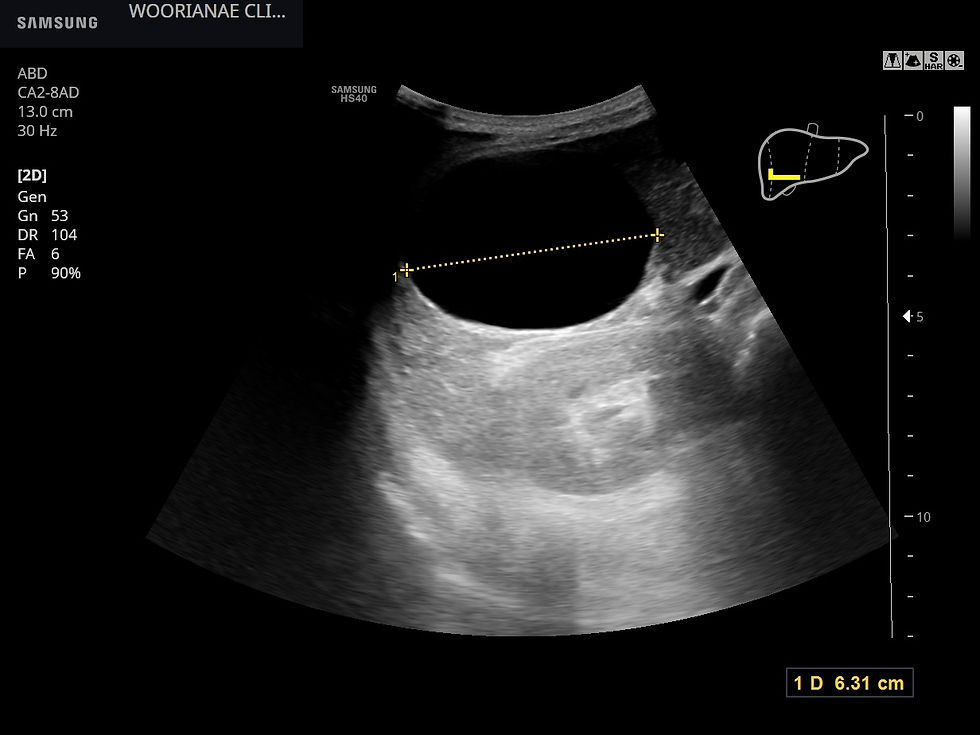

초음파 시행

우엽 5번 구역에 큰 간낭종, 이외에 4~5개의 낭종 및 고음영 종괴 (일반적으로 혈관종 소견) 가 2개 있었다.

간 아래 낭종에 의해 담낭의 구별이 어려운데 사이 공간에 위치하고 있다.

내부에 찌꺼기, debris 가 있는 낭종이 배꼽 높이까지 내려와 관찰되는데 크기는 7*7 cm 정도